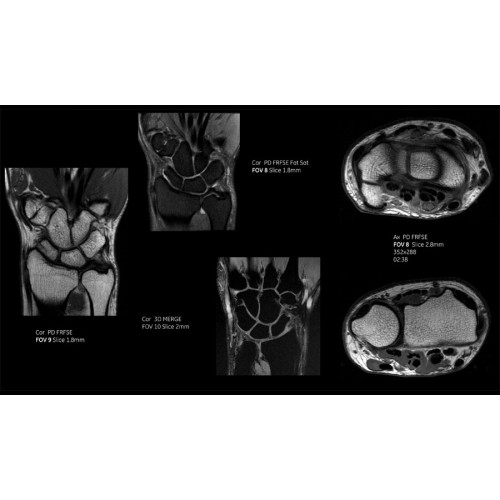

Детализация изображений

Система SIGNA Pioneer воплощает поразительные достижения в области визуализации. Передовая технология Total Digital Imaging (TDI) позволяет добиться большей четкости изображений и на четверть повысить соотношение сигнал/шум.

TDI построена на трех базовых компонентах:

• Технология Direct Digital Interface (DDI) использует независимый аналого-цифровой преобразователь для оцифровки сигнала от каждого из 97 радиочастотных каналов, что обеспечивает значительное увеличение качества за счет уменьшения фонового шума.

• Технология Digital Micro Switching (DMS) — это следующее поколение технологий радиочастотных катушек, основанное на замене аналоговых схем блокировки сверхбыстрыми микропереключателями (MEMS), что делает возможным быстрое переключение катушек для дальнейшего расширения возможностей визуализации с нулевым TE.

• Технология Digital Surround Technology (DST) — это новая технология объемной оцифровки данных, объединяющая сигналы от каждого элемента катушки. Прекрасное соотношение сигнал/шум и чувствительность поверхностных катушек в сочетании с превосходной однородностью и высокой проникающей способностью встроенной радиочастотной катушки — все это позволяет создавать качественные изображения не только позвоночника, но и всего тела.

Помимо технологии 97 РЧ-каналов, SIGNA Pioneer использует магнит 3.0Т высокой однородности, предназначенный для повышения качества визуализации во всех областях, а также закладывающий прочный фундамент для долгосрочных инвестиций и роста клинических возможностей.